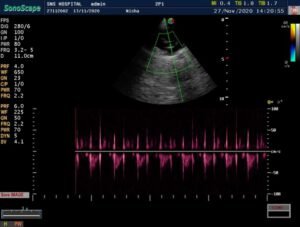

Early neonatal ultrasound cranium and fetal echo performed – was found within normal limits